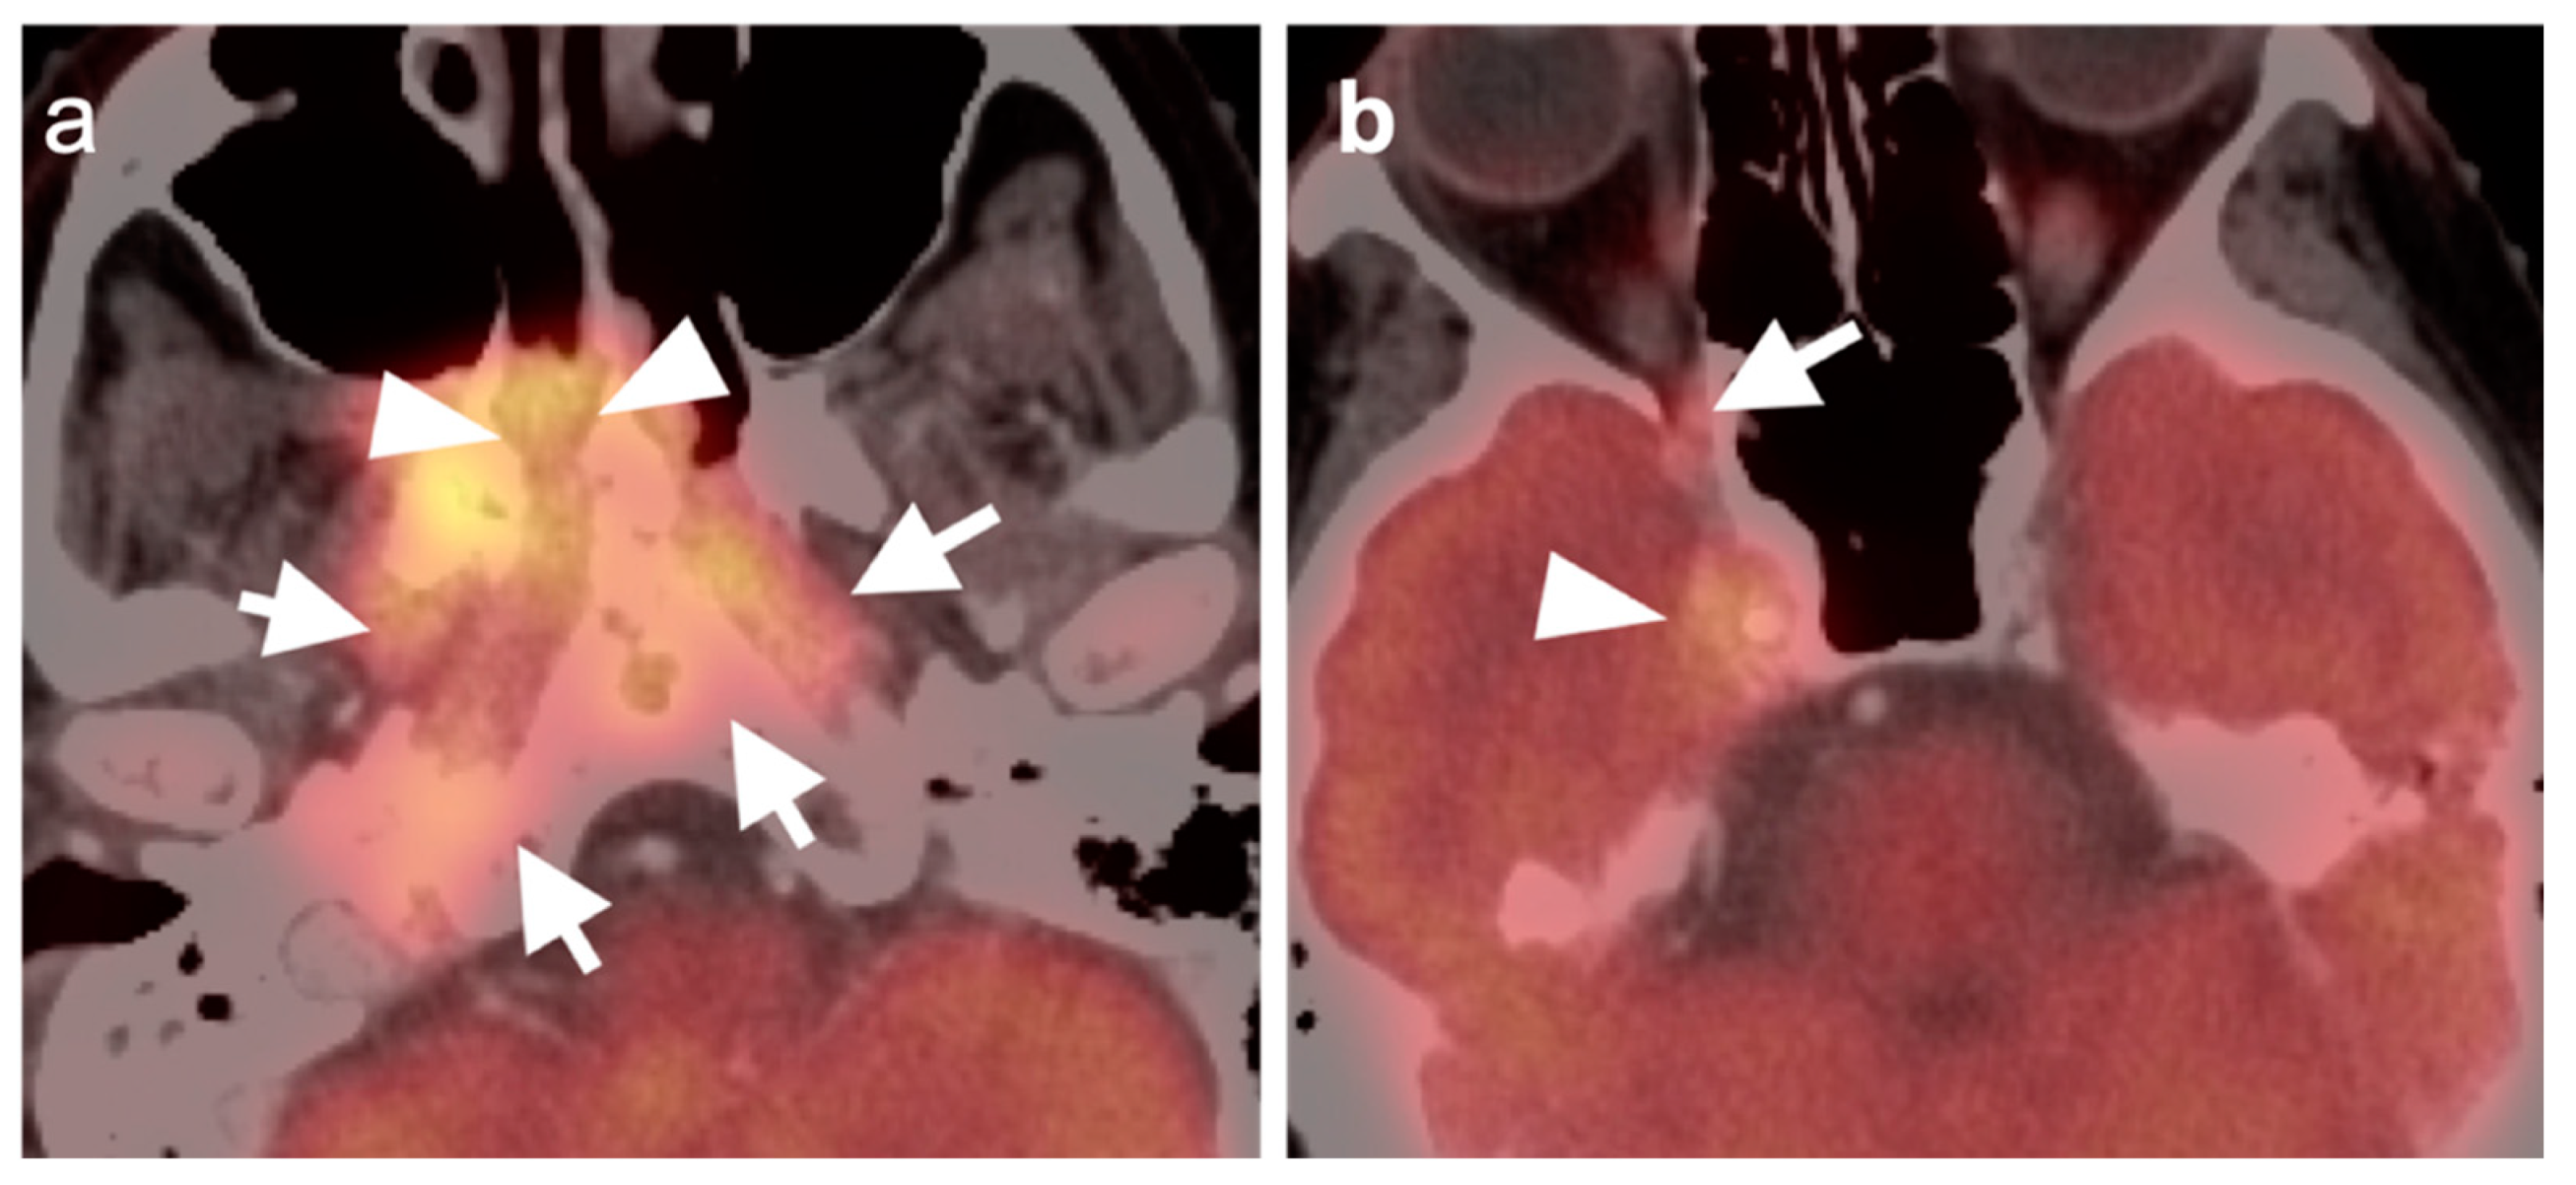

2.5. Major and Minor Salivary Gland, Lacrimal Gland Tumors

- Adenoid cystic carcinoma